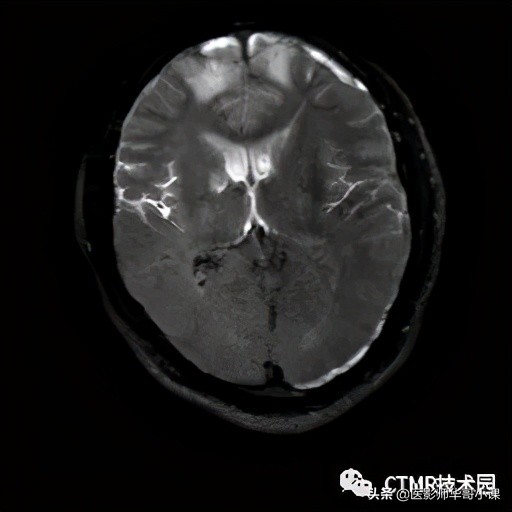

由序列的研究可知,是先施加 180° 反转脉冲,等待 TI 时间再进行信号采集。那么由于运动,就产生了部分被反转,部分未被反转。以后面的被反转为基准来看,那么前面的就是未被反转,由于病人运动的维度不只是 2D 平面内晃动,而是 3D 空间的乱动,抬头,扭动等。那么很容易导致脑脊液未被反转的空间组织进入成像范围,这将导致脑脊液呈高信号。正是由于施加 180° 反转脉冲时会动,采集图像时也会动,而且都是3D维度的运动,那么最终得到的图像的空间是两者的相交。

可以看到未被 180° 脉冲激发的组织进入了采集范围。当然这只是模式图,在扫描时病人的运动可能更复杂,我记得在后面的扫描过程中,病人都脱离线圈了,从线圈中滑出来了……